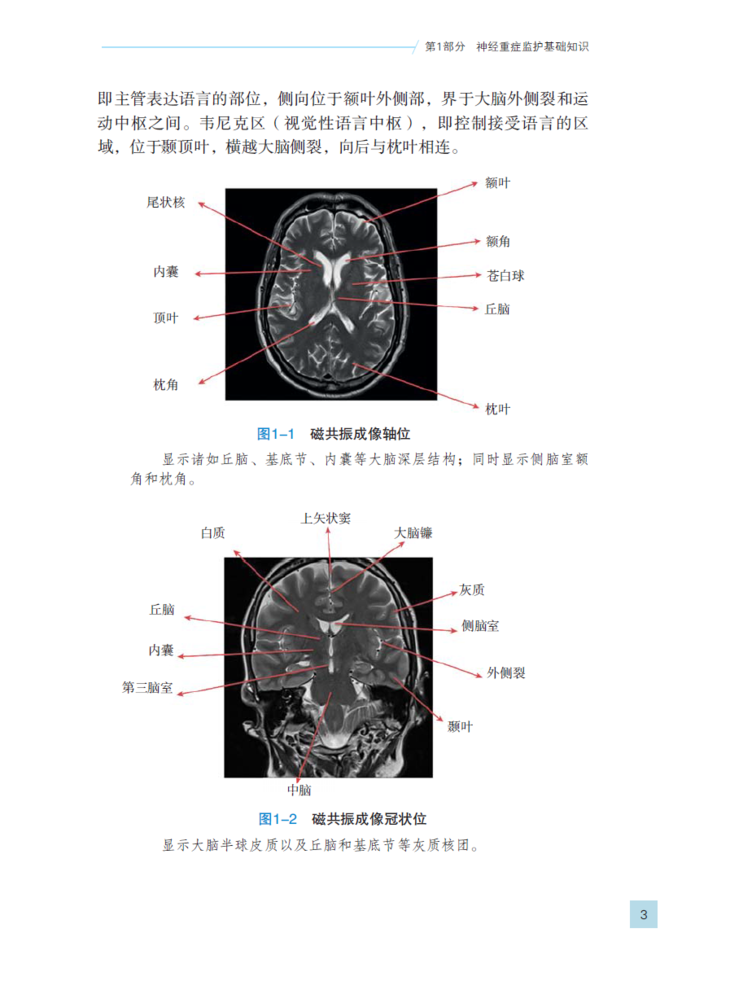

本书采用了灵活多变的行文方式,简化并归纳了神经重症监护领域各方面的知识。这些复杂的知识常常令人望而生畏。全书插入了大量的图和表格,并结合大量的数据,对神经系统疾病的病理生理、诊断以及治疗原则等方面进行了言简意赅地解析,为这一新生医学领域提供了浅显易懂的阐释。书中多帧高清晰度的放射影像插图演示了各类神经内外科疾病的影像学表现。此外,本书对神经重症监护领域的重要临床试验和研究进行了概述,同时还提供了基于循证医学的评价和总结。